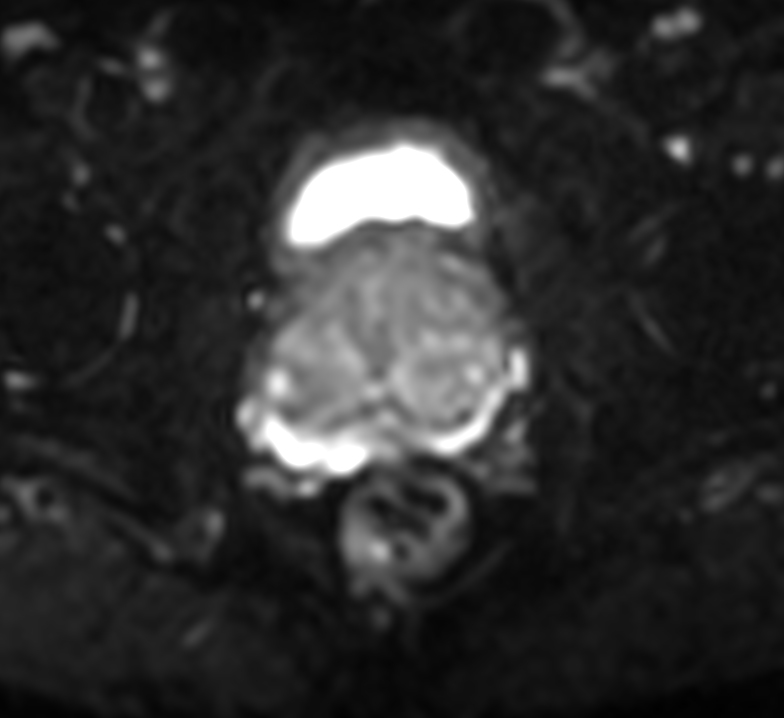

Axial DWI (ADC)

Axial DWI (eADC)